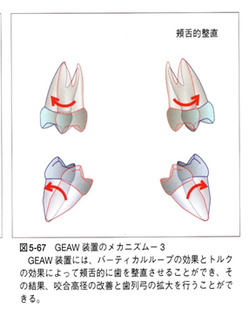

その為にMEAW(マルチループ)を利用して歯を立体的に動かしています。

MEAW(マルチループ)を利用して歯を動かす隙間の作り方は2種類あります。

②ふたつ目は以下の様な原理です。

①では歯が近心側に綺麗に傾いた場合ですが、歯が内側(舌側)に傾く事もあります。

この場合もMEAW(マルチループ)によって内側(舌側)に傾むいた歯を起こしていきます。